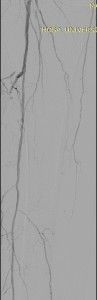

Nesta última imagem, observa-se o fluxo pela Fibular opacificando parcialmente o Arco Plantar via ramos tarsais. Note-se que o extenso grau da doença aterosclerótica obstrutiva ainda impede a opacificação das artérias do ante-pé. Apesar destes achado angiográficos a paciente referiu significativo alívio da sintomatologia dolorosa.